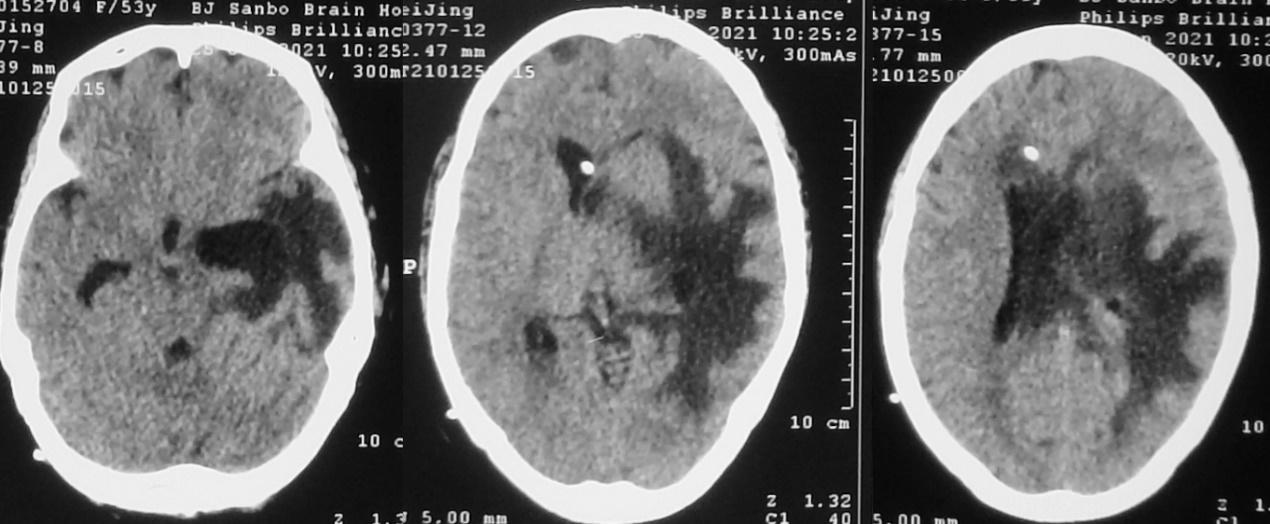

当天,即发病后78天,即脑脓肿清除术后第49天,脑室腹腔分流术后第13天,即2021年1月26日,行第3次左侧颞角外引流术。但术后患者意识无明显改善。2021年1月28日患者再次出现发热,体温38.4℃,反应迟钝,复查头颅CT见左侧脑室颞角缩小,但右侧脑室较前扩张( 图-28 )。第3次左侧脑室颞角引流后脑脊液细菌培养回报为表皮葡萄球菌。给予抗炎治疗。

经治疗后患者发热好转,神志清醒,于第3次左侧脑室颞角引流后6天,即2021年2月1日,拔除了左侧颞角引流管。但发病后88天,即脑脓肿清除术后第59天,脑室腹腔分流术后第23天,拔除左侧颞角引流管后3天,即2021年2月4日,患者再次发热,体温38.3℃。患者间断嗜睡,复查头颅核磁共振( 图-29 )提示左侧脑室颞角扩张。于2021年2月4日,当天行第4次左侧脑室颞角穿刺外引流术。

图-29: 2021年2月4日头核磁

患者术后仍间断发热,呈嗜睡状态,反应迟钝。发病后92天,脑脓肿清除术后第63天,脑室腹腔分流术后第27天,第4次左侧颞角外引流后4天,即2021年2月8日,复查头颅CT见右侧脑室仍稍扩张,左侧脑室颞角缩小( 图-30 )。

图-30: 2021年2月8日头CT

发病后94天,在北京某脑科医院治疗81天,行丘脑脑脓肿清除术后第65天,脑室腹腔分流术后第29天,第4次左侧颞角外引流后6天,即2021年2月10日,患者仍间断发热,反应迟钝,在主管医生的推荐下,患者转入北京北亚骨科医院的李小勇脑脊液科。